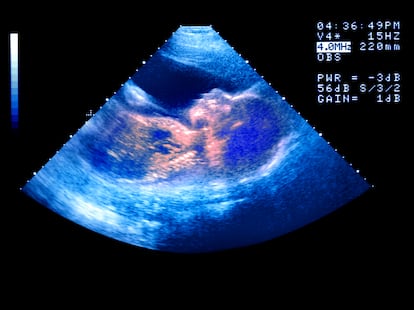

Recientemente han aparecido anuncios en redes sociales y en espacios públicos, como en el metro de Nueva York, que presentan la selección genética de embriones como una forma de tener un “bebé más sano” e incluso un “bebé mejor”. Algunos lemas, como “Ten tu mejor bebé” o “genéticamente optimizado”, sugieren que sería posible escoger embriones con mejores predicciones de altura, inteligencia o menor riesgo de enfermedad. Para entender el debate respecto a la selección genética hay que empezar por lo básico. Desde hace años existen técnicas que permiten analizar embriones antes de transferirlos durante tratamientos de fertilidad. Su objetivo original es médico: ayudar a familias con enfermedades hereditarias graves evitando transmitirlas a sus hijos. En estos casos, se pueden detectar alteraciones genéticas concretas y seleccionar embriones que no las tengan. Este uso está regulado en muchos países.

Aun así, algunas parejas recurren a servicios en el extranjero o contratan análisis por su cuenta a empresas como Orchid Health, Herasight, Heliospect o Genomic Prediction. Estas compañías ofrecen un screening genético de los embriones que estima riesgos de padecer determinadas enfermedades y que, en teoría, permitiría elegir cuál implantar según probabilidades de salud, rasgos físicos u otras características. Aunque suena futurista y tranquilizador, los especialistas advierten de varios riesgos.